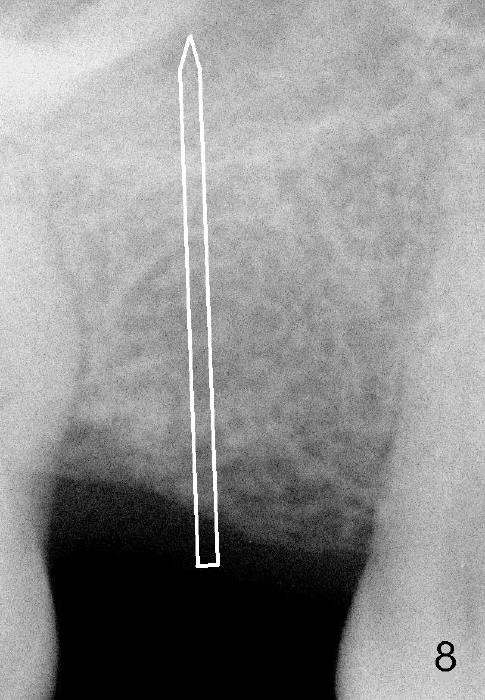

Another drawback of the implant placement is that the trajectory is off and distal (Fig.3-6), probably due to the low bone density in the distal aspect of the socket prior to extraction (Fig.7 CT sagittal section; MB: mesiobuccal root). The pilot drill must inadvertently have drifted distally and to the less dense bone (Fig.8). If it had been found, it could have been corrected early (Fig.9 red arrow). The trajectory could have been corrected immediately after the 2.6 mm expander (Fig.10). Ideally the pilot drill (Fig.11arrow) should be placed slightly mesial to the presumably mid edentulous line (red line) and only half of the length. If the trajectory is right, continue osteotomy (Fig.12). If not, correct it immediately.